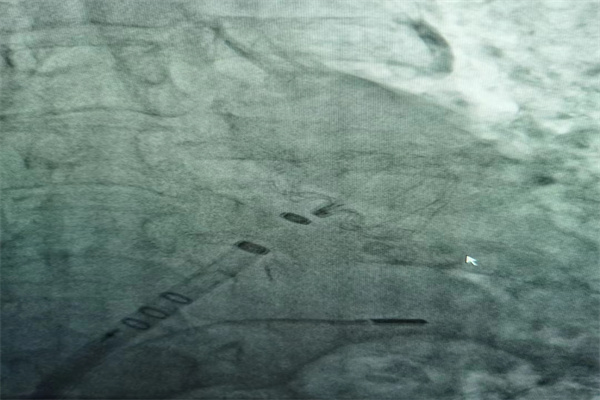

術(shù)前,心臟CTA精準(zhǔn)分析,術(shù)中ICES(心腔內(nèi)超聲)高清引導(dǎo),歷經(jīng)右心房—房間隔—左心房—左心耳,然后對(duì)劉奶奶左心耳進(jìn)行多維度測量,再經(jīng)DSA多體位造影,確定為劉奶奶左心耳開口22mm,深度25mm。

歷時(shí)2個(gè)半小時(shí),最終為劉奶奶順利植入WATCHMAN 27mm封堵器,術(shù)后再經(jīng)ICES觀察封堵效果良好,壓縮比18 %,符合PASS原則。整個(gè)手術(shù)過程,劉奶奶完全清醒、無不適感。